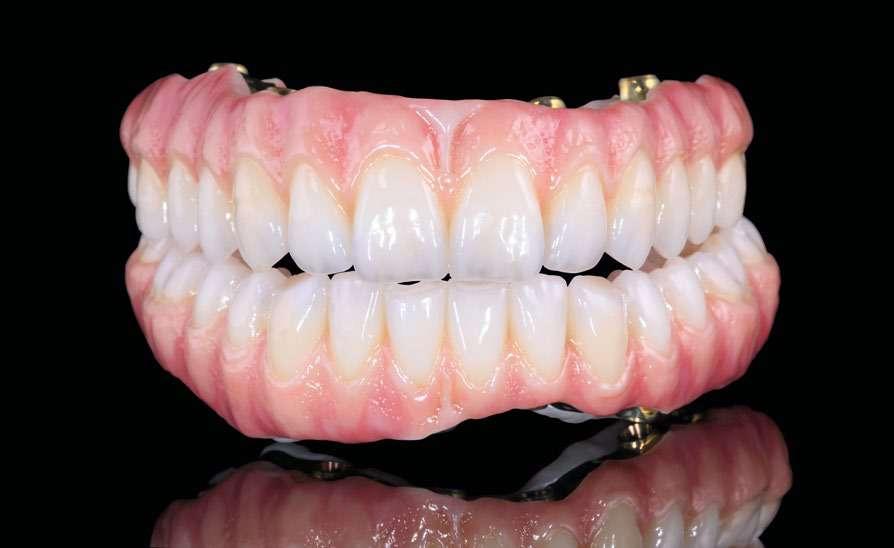

Transcurridos 3 meses desde la cirugía inicial, podemos comenzar a confeccionar la prótesis definitiva que se realiza sobre el mismo transepitelial, para evitar romper las uniones epiteliales formadas a ese nivel y conservar el hermetismo de los tejidos blandos periimplantarios. La prótesis final es una corona E-Max, totalmente cerámica, cementada a una interfase, atornillada al transepitelial unitario. Con esta solución alcanzamos una estética correcta para el

sector antero-superior a la vez de que mantenemos los tejidos blandos periimplantarios sin retracciones, asegurándonos además un correcto ajuste y hermetismo entre la prótesis y el implante (figuras 15-17).

El paciente continúa en seguimiento posterior, con revisiones cada 6 meses durante los dos primeros años. En todas ellas no existe complicación ni pérdida ósea asociada al implante, tal como podemos ver en la radiografía de control a los dos años (figura 18).

Figura 13. Cierre primario a los 3 días con el provisional de carga inmediata.

Figura 14. Radiografía tras la colocación de la prótesis provisional de carga inmediata.

Figuras 15 y 16. Imágenes de la corona definitiva colocada en el paciente tras los 6 meses de la inserción del implante y la prótesis de carga inmediata.

Figura 17. Radiografía tras la colocación de la prótesis definitiva.

Figura 18. Radiografía de control a los dos años, donde observamos el implante y la estabilidad del tratamiento.

Cinco años después, llevamos a cabo un nuevo cone-beam y en el podemos observar la evolución del implante y de la sobre-corrección vestibular llevada a cabo en la cirugía inicial. Tanto el implante como el hueso que se ha formado a nivel vestibular fruto del injerto empleado está estable y se mantiene sin pérdida ósea asociada, tal como mostramos en los cortes del cone-beam

inicial y final a los 5 años de seguimiento (figura 19). En las imágenes intraorales tomadas en este punto del seguimiento se constata el éxito del tratamiento (figuras 20 y 21). En la radiografía periapical, observamos con mayor detalle la regeneración del tejido óseo del diente en posición 11 así como la estabilidad ósea del implante (figuras 22 y 23).

en vestibular.

20 21

Figura 19. Imagen inicial del cone-beam y final con el implante cargado a los 5 años de seguimiento con la estabilidad del implante y del hueso generado mediante el injerto

Figuras 20 y 21. Imagen inicial y final de paciente tras 5 años de seguimiento. En ellas observamos la estabilidad del tratamiento logrado con el implante.

Figuras 22 y 23. Radiografía periapical inicial y a los 5 años de seguimiento.